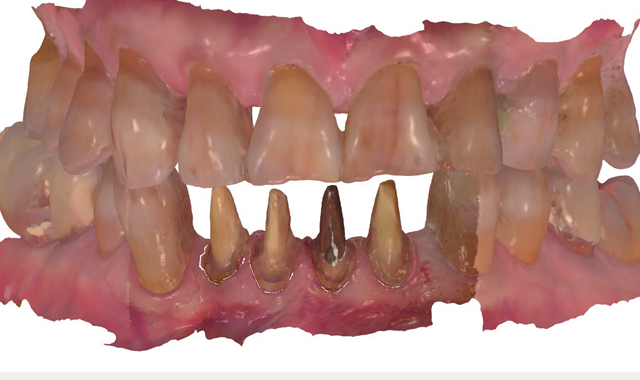

An 88-year-old man presented for restoration of tooth #25, which was fractured and had been endodontically treated (Fig. 1). A thorough intraoral and radiographic examination was performed, which revealed damage to the remaining anterior mandibular teeth incurred over the years as a result of scaling and curettage (Fig. 2). This damage to the

Fig. 2

root surface of the lower incisors-which was visible on the radiograph (Fig. 3)-is known as “Riffle-ization.” Described by Dr. Riffle as a technique for removing every last bit of calculus during repeated root scaling, what is now known as “Riffle-izing," ultimately-over the years-changes the shape of the neck of the tooth to resemble an hour glass.

Therefore, based on the clinical and visual evaluation, the preferred treatment would be to restore the fractured #25 with a post and crown and four splinted crowns to restore the anatomy of the four incisors and increase their resistance to both mobility and fracture.